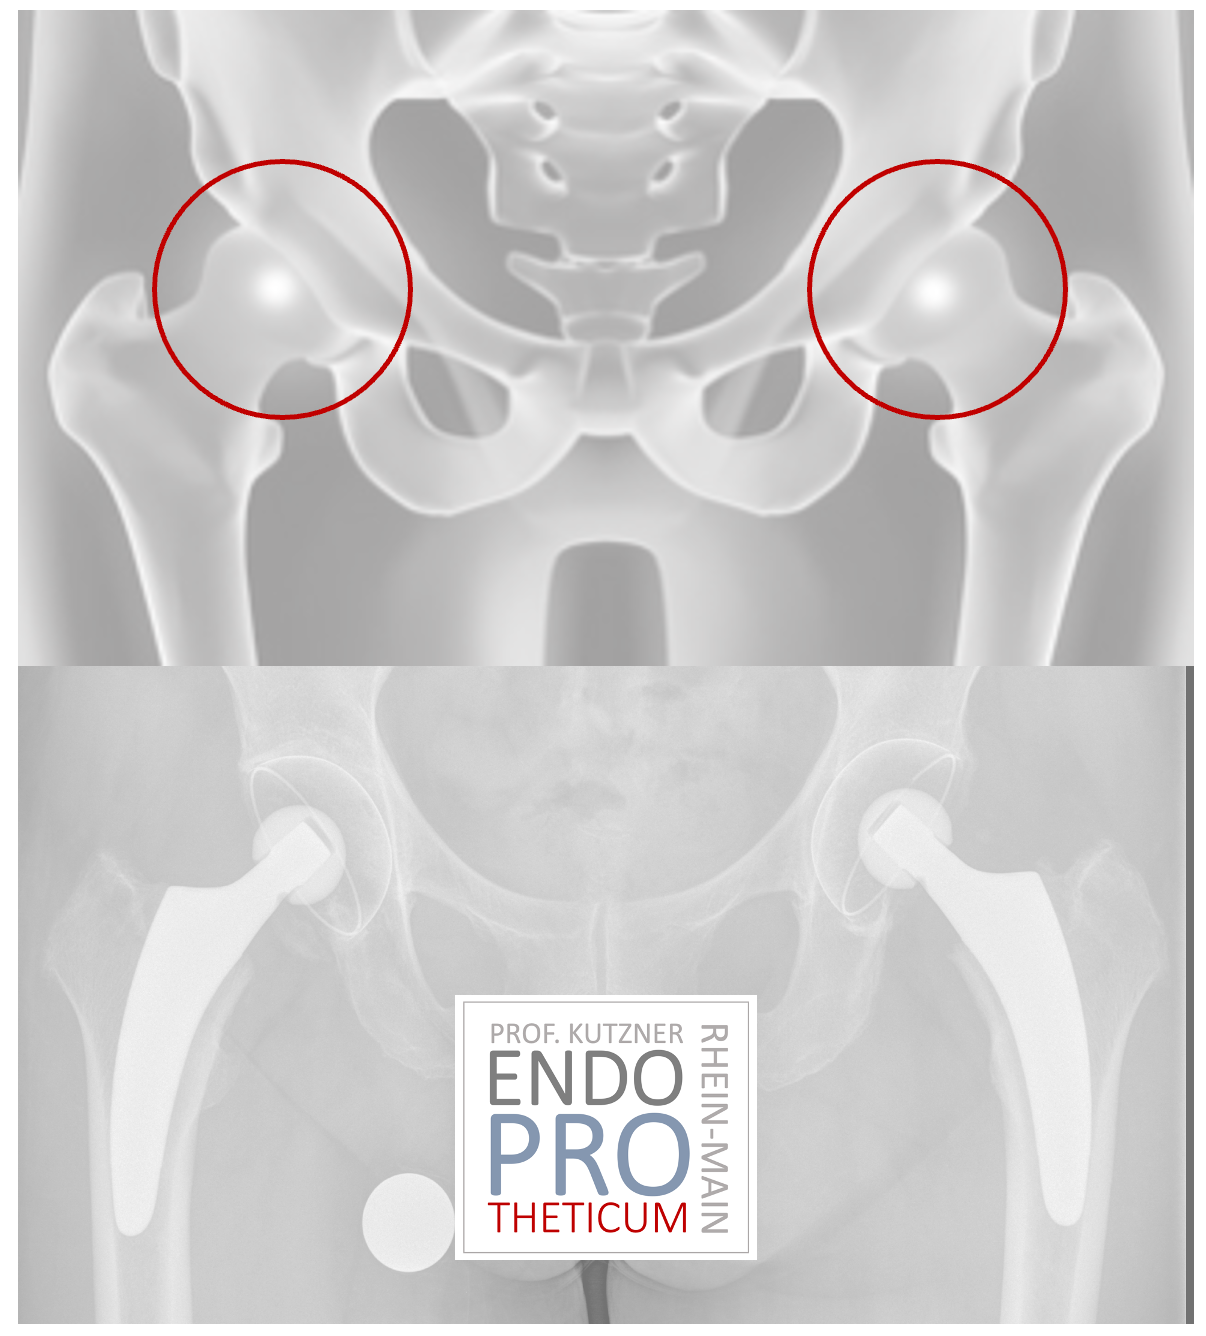

أصبحت الأطراف الاصطناعية ذات العمود القصير ذات شعبية متزايدة في السنوات الأخيرة. تهدف عملية زرع الأطراف الاصطناعية ذات الجذع القصير إلى الحفاظ على العظام وخلق ظروف مواتية للمراجعة دون تغيير المفاهيم الأساسية لتقويم مفاصل الورك التقليدية.

تم تطوير الأطراف الاصطناعية ذات العمود القصير منذ عقود مضت لضمان أسلوب زرع لطيف على العظام والأنسجة الرخوة؛ ظهرت العديد من الابتكارات والتعديلات في السوق في السنوات الأخيرة.